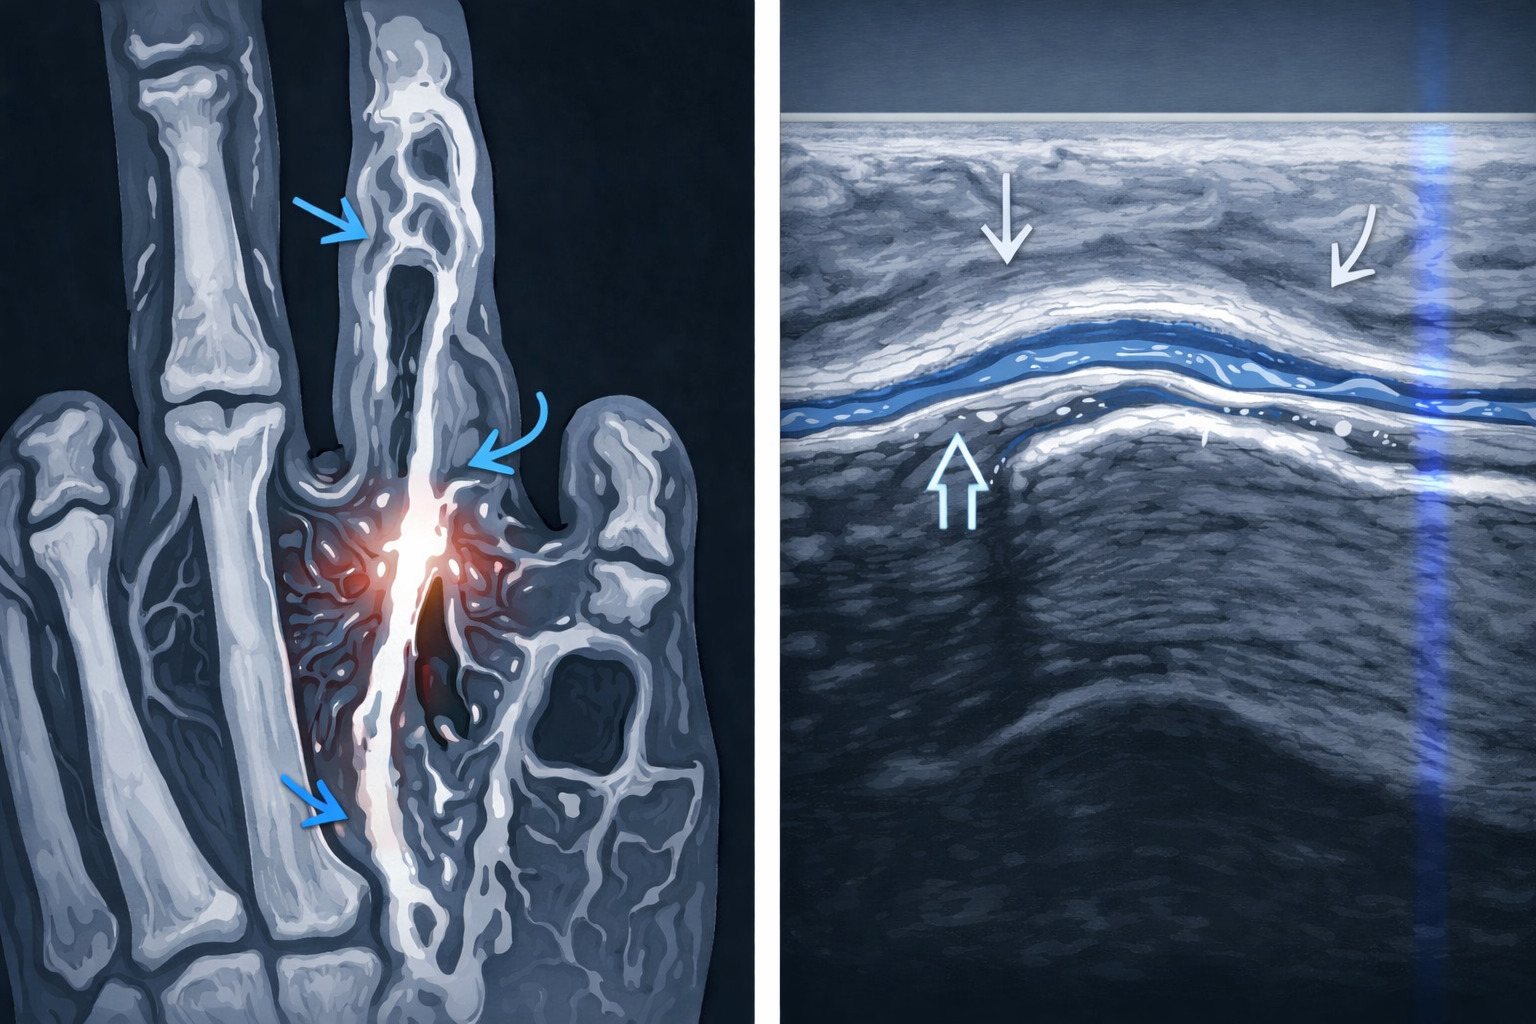

Лабораторные анализы обычно не требуются. Применяются инструментальные методы диагностики:

- Чтобы исключить повреждения костей, выполняют рентгенографию в двух проекциях. Это стандартная процедура, которая помогает точно определить, есть ли трещина или перелом.

- Если снимок «чистый», но палец болит, врач может направить на УЗИ. Этот метод показывает состояние связок, сухожилий, наличие внутренних гематом.

- В сложных случаях используется МРТ, которое дает точное изображение тканей, помогает выявить повреждения, не заметные на рентгене.

- Для оценки состояния костной ткани, выявления скрытых микротрещин проводится компьютерная томография.